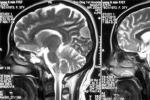

3.CT或MRI掃描

是本病診斷的主要手段,CT掃描可顯示出上矢狀竇旁圓形,等密度或高密度影,增強掃描時可見密度均勻增高,基底與矢狀竇相連,有些患者可見瘤周弧形低密度水腫帶,另外,CT掃描骨窗像可顯示顱骨改變情況(圖2),MRI與CT相比,在腫瘤定位和定性方面均有提高,腫瘤在T1加權像上多為等信號,少數為低信號;在T2加權像上則呈高信號,等信號或低信號;腫瘤內部信號可不均一;註射Gd-DTPA後,可見腫瘤明顯強化,MRI掃描還可清楚地反映腫瘤與矢狀竇的關系.